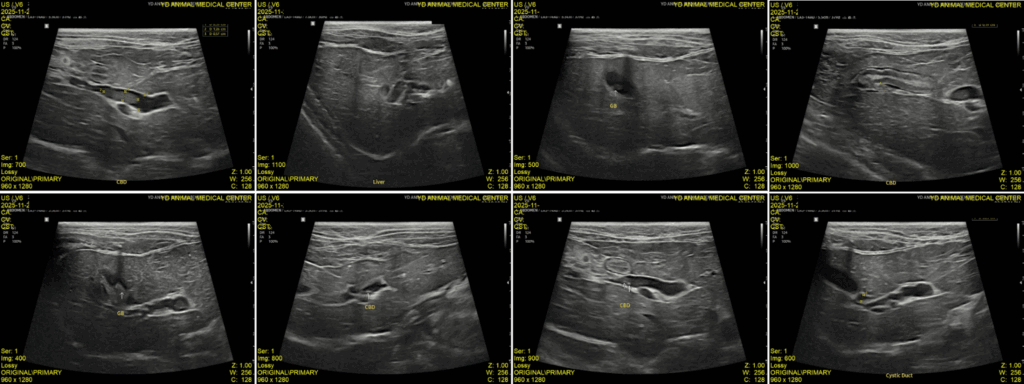

이어서 진행한 복부 초음파 검사에서는 췌장염 소견과 함께 위벽 및 일부 장 근층 비후가 관찰되었고, 담낭관(Cystic duct)과 총담관(CBD)이 심하게 확장되어 있으며 내강 내 슬러지가 확인되었습니다. 또한 담낭 내에는 중등도의 슬러지와 담석이 있었고, 간 내 담도 결석과 전반적인 간 에코 증가도 함께 확인되었습니다.

내원당시 복부초음파 검사 결과 / 출처: 강서YD동물의료센터